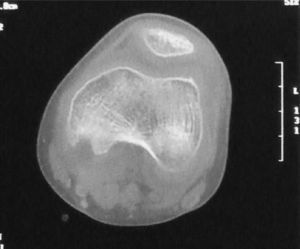

Nine days after admission, an MRI was performed which showed a moderate collection in the joint cavity, mainly in the intercondylar notch and showing contrast uptake compatible with synovial proliferation (Fig. 1). In the back of the left femoral condyle, we identified a small lytic lesion of approximately 7mm×5mm in diameter, associated with a collection that had peripheral contrast uptake, compatible with small bone inflammation. A CT was performed within 20 days, and a 6-mm lytic lesion was seen in the posterior aspect of the medial femoral condyle, with involvement of the cortical bone without any periosteal reaction observed (Fig. 2).